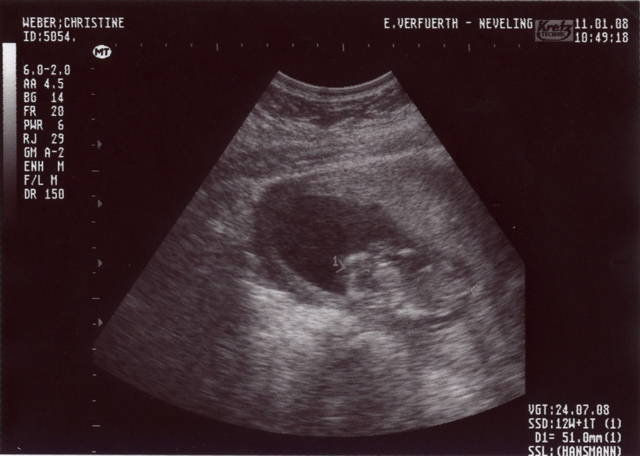

Mama und Papa haben mir freundlicherweise Bilder von meiner Ein-Zimmer-Wohnung zur Verfügung gestellt. Erstellt wurden die mit so einem Ding namens Ultraschall. Ich weiß nur noch, dass ich in den ersten Wochen von dem Teil überhaupt nicht begeistert war und mich immer ganz klein gemacht habe, wenn Mama und Papa schon wieder knippsen wollten. Aber wer lässt sich schon gern freiwillig in seine Privatsphäre schauen?

In der 12ten Woche war ich schon 51mm groß … und man konnte meinen Herzschlag als Blinken sehen.